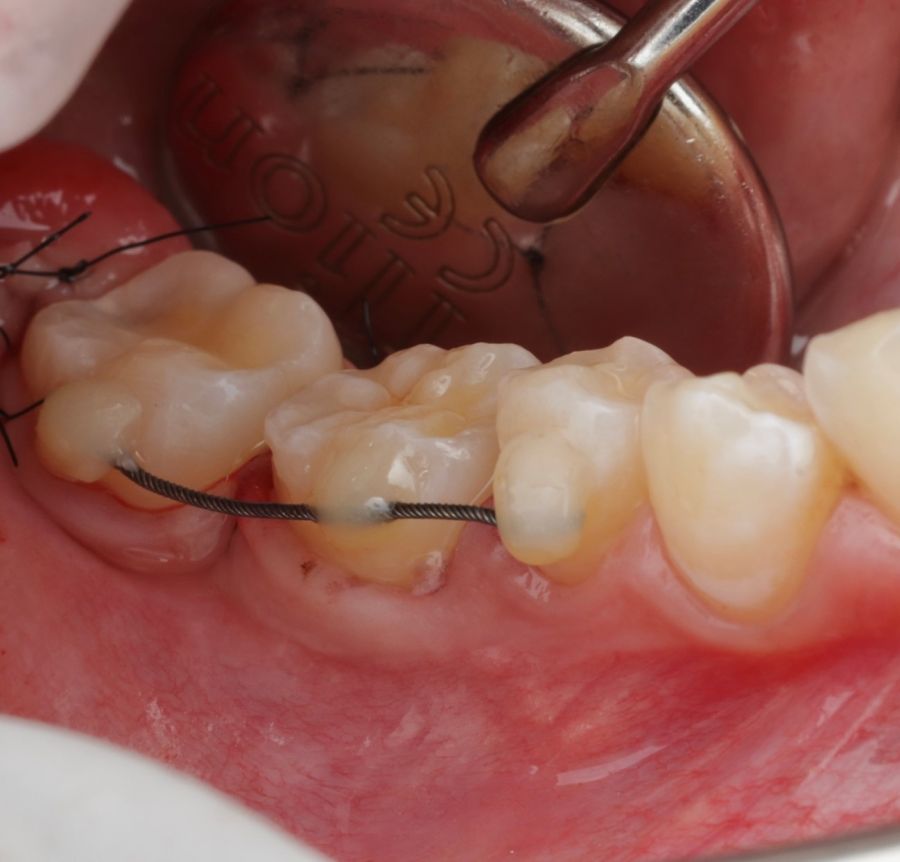

En la revisión sistemática realizada por Barrientos y cols.10, se analizan puntos clave para el protocolo de AD, como los diferentes materiales de fijación del autotrasplante, alambre, resina, sutura, fijación ortodóntica o férulas acrílicas. La tasa de éxito del procedimiento varían entre un 76% y un 95%. La necesidad del tratamiento de conductos, en el 21,1% de dientes no se realizó endodoncia, principalmente en casos con ápice abierto y la tasa de éxito fue más alta cuando la endodoncia se efectuó alrededor del primer mes postoperatorio (en dos semanas: 95,75%; de 7 días a 4 semanas: 90%, y de 6 días a 4 semanas 92,5%. En cuanto a la supervivencia de los dientes trasplantados se apreció que la tasa de éxito disminuye con el paso del tiempo (más de siete años 84%).10.

La confección de la réplica 3D del diente se ha de realizar con material biocompatible y esterilizable mediante radiación gamma y beta. La ventaja del modelo estereolitográfico es minimizar el tiempo extraoral del diente donante, el daño al ligamento periodontal, así como poder remodelar el alveolo receptor sin usar el diente donante5,13,14.